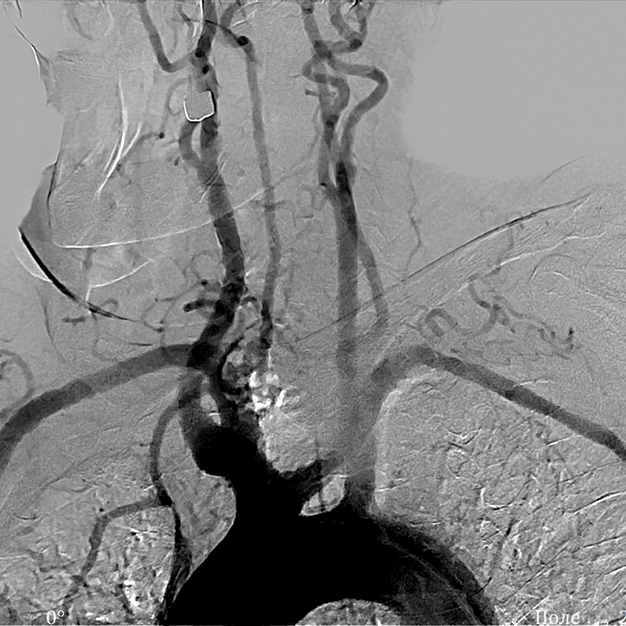

The high image quality provided by mobile C-arm systems is achieved due to a digital imaging system, which allows seeing even the smallest defects and pathologies. A mobile C-arm system model with a flat panel detector provides for imaging of even the smallest vessels. The modes of pulsed fluoroscopy, lowered dose fluoroscopy, and special quality fluoroscopy in combination with the wide APR program range, which considers the patient’s age and the body build, allows obtaining a high-quality image with the minimum exposure dose.

Thanks to an effective cooling system of the X-ray tube assembly, the system provides for a long period of X-ray control, which determines the use of the system for a wide range of diagnostic and medical-surgical manipulations on the heart and vessels. The subtraction angiography mode, the vascular package, the routing, and mask selection option create the necessary conditions for successful use of the system in coronary angiography, angiography, and control of electrophysiology procedures.